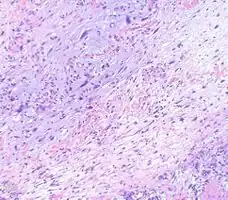

Myxofibrosarcoma-pathology